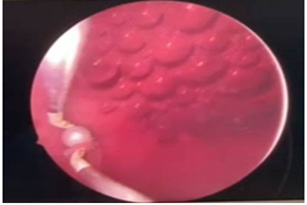

Cystoscopy was done to detect mucosa lesions in bladder; the whole mucosa was congested and red. There were multiple hemorrhagic areas in whole bladder mucosa; it was bled on touch. There was no focal ulcer or tumor. Therefore, generalized congested mucosa, hemorrhagic areas were probably due to DIC or CMV cystitis or candida cystitis or bacteria cystitis. The color of urine coming from Vescio-ureteric orifice of graft kidney was clear. Hemostasis was done with Ball electrode; bladder wash out was done with Tomey’s glass syringe. Figure 9-15 reveal cystoscopy findings. Abdominal tomogram was done; it revealed a swollen allograft kidney with air in the renal pelvis and renal vessels and subcapsular area suggestive of emphysematous allograft pyelonephritis. And, air along bladder wall was seen indicating emphysematous cystitis. They are illustrated in (Figure 16-19).